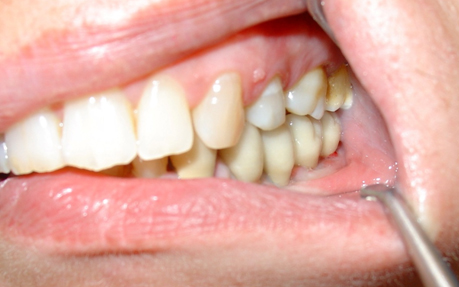

Siguiendo el protocolo de actuación, se hace la historia clínica, la ficha implantológica, se solicitan análisis de laboratorio de rutina y una ortopantomografía, así como periapicales de la zona.se toman impresiones superiores e inferiores con alginato y se vacían en yeso piedra. Se toman registros con la ayuda de un arco facial y se montan los modelos en articulador semiajustable. Después del análisis de los modelos y de las radiografías se decide colocar cuatro implantes monoblock Q-implant Trinon de 3,5 mm de diámetro y 12 mm de largo, para ser cargados de forma inmediata por un puente metal-cerámica cementado.(F1)

Se realiza un encerado diagnóstico en el laboratorio dental respetando los datos obtenidos durante el estudio del caso y en base al mismo se confecciona una férula quirúrgica convencional. Se colocan los cuatro implantes dentales mediante cirugía mínimamente invasiva sin colgajo. Al ser implantes dentales de una sola pieza, los muñones protéticos expuestos se fresan en boca con alta refrigeración para obtener un correcto paralelismo entre los mismos, y lograr así un ajuste sin tensiones de la prótesis fija implantosoportada.(F2)